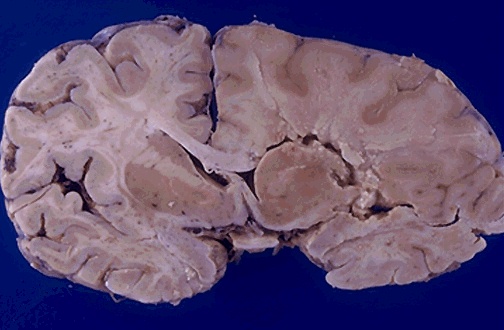

The subacute (intermediate) infarct seen here at the right shows edema with obscured structural outlines and swelling that shifts the midline to the left. There is liquefactive necrosis with beginning formation of cystic spaces.